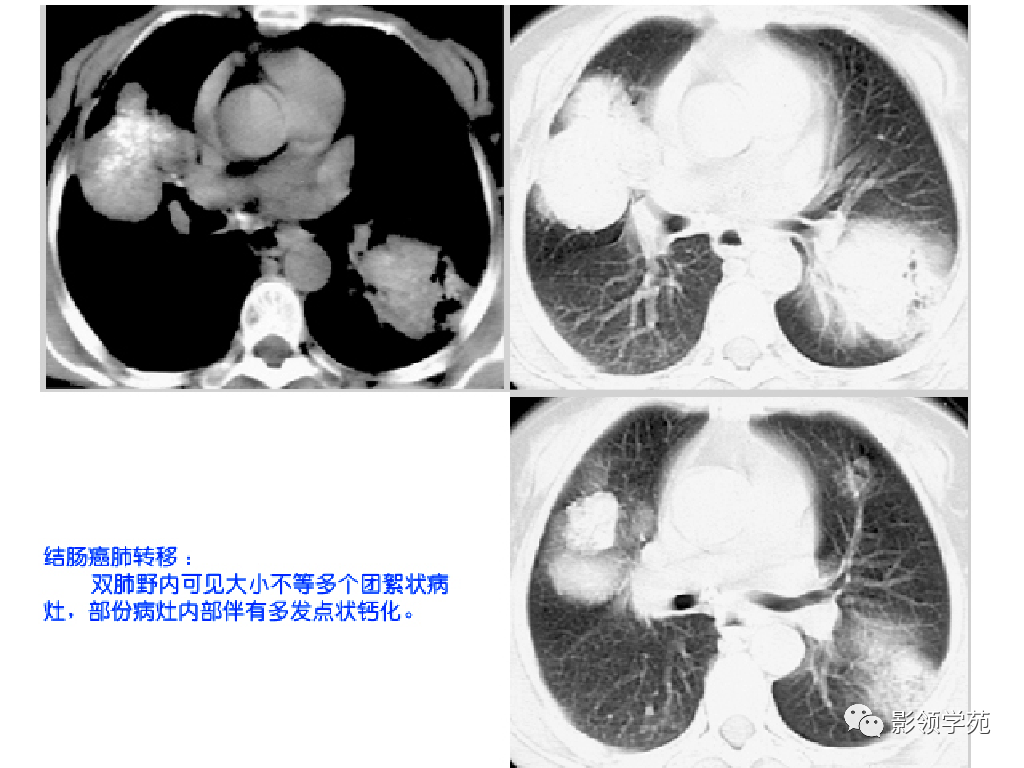

多发或单发结节,大小不一,边缘较清楚。少数结节伴出血时出现晕轮征,即有略高密度影像环绕结节,使病变边缘模糊。病变有钙化常见于骨肉瘤或软骨肉瘤转移。转移瘤亦可表现为空洞。两肺多发的小结节影具有随机分布的特点,HRCT显示结节位于小叶中心、小叶间隔、支气管血管束及胸膜,结节大小不均匀。

肺转移瘤。肺窗像(A)示双肺野可见大小不等的圆形高密度结节影,纵隔增宽;纵隔窗像(B)示肺内肿块呈实性,纵隔满布大小不等的肿大淋巴结

CT诊断:甲状腺癌双肺多发转移